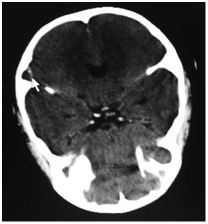

In the presence of clinical mastoiditis, a CT scan should be performed to evaluate for an unappreciated subperiosteal abscess or coalescent mastoiditis (Figure 1 & Figure 2). MRI is also useful in mastoiditis cases (Figure-3), but it is not done routinely. CT scan can demonstrate subperiosteal abscess and possibly the cortical defect in the mastoid.

Figure 3 MRI showing (arrow) mucosal thickening in the left mastoid air cells.